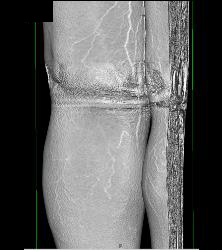

Bakers Cyst